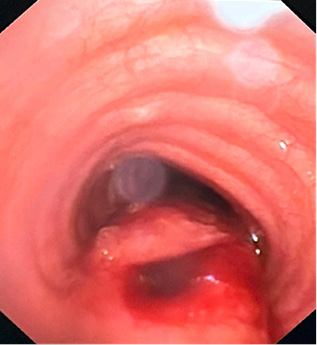

No pneumothorax was observed. Traumatic tracheal rupture was suspected, and emergency tracheobronchial fiber endoscopy confirmed the diagnosis. It showed a posterior tracheal transmural rupture 1 cm long, located 4 cm above the carina, covered with small tissue that opened in inspirium (Figure 5). The patient was admitted in the Intensive Care Unit, oxygen therapy started, and vital signs were monitored.

poser12.jpg Figure 5. Posterior tracheal transmural rupture 1 cm long